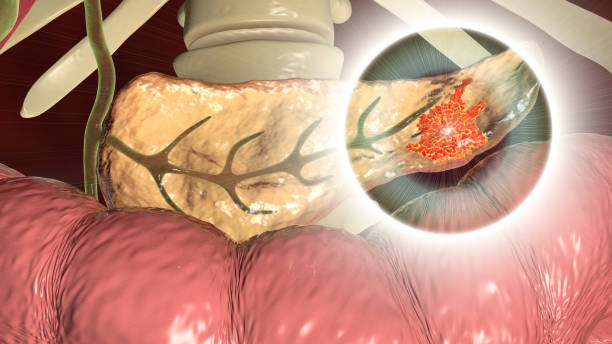

췌장암 초기증상 5. 췌장염

췌장암 초기증상 열 번째는 췌장염인데요. 췌장염은 췌장암으로 이어질 수 있어요. 이것은 만성 췌장염과 급성 췌장염 모두에 적용돼요. 특히나 만성 췌장염이 있다면 정기적인 췌장암 검진을 받는 것이 좋아요.

췌장암 초기증상 다섯 번째는 소화장애인데요. 종양이 자라면서 대변 형태의 변화인데요. 많은 양의 대변과 함께 물에 뜨는 밝은 색의 기름이 있 다고 알려져 있어요. 암세포가 위장으로 전이되면 식후 불쾌한 통증, 메스꺼움 또는 구토를 동반하는데 단순 소화불량으로 치부하는 경우도 있지만 정밀 검사를 받을 필요가 있어요.